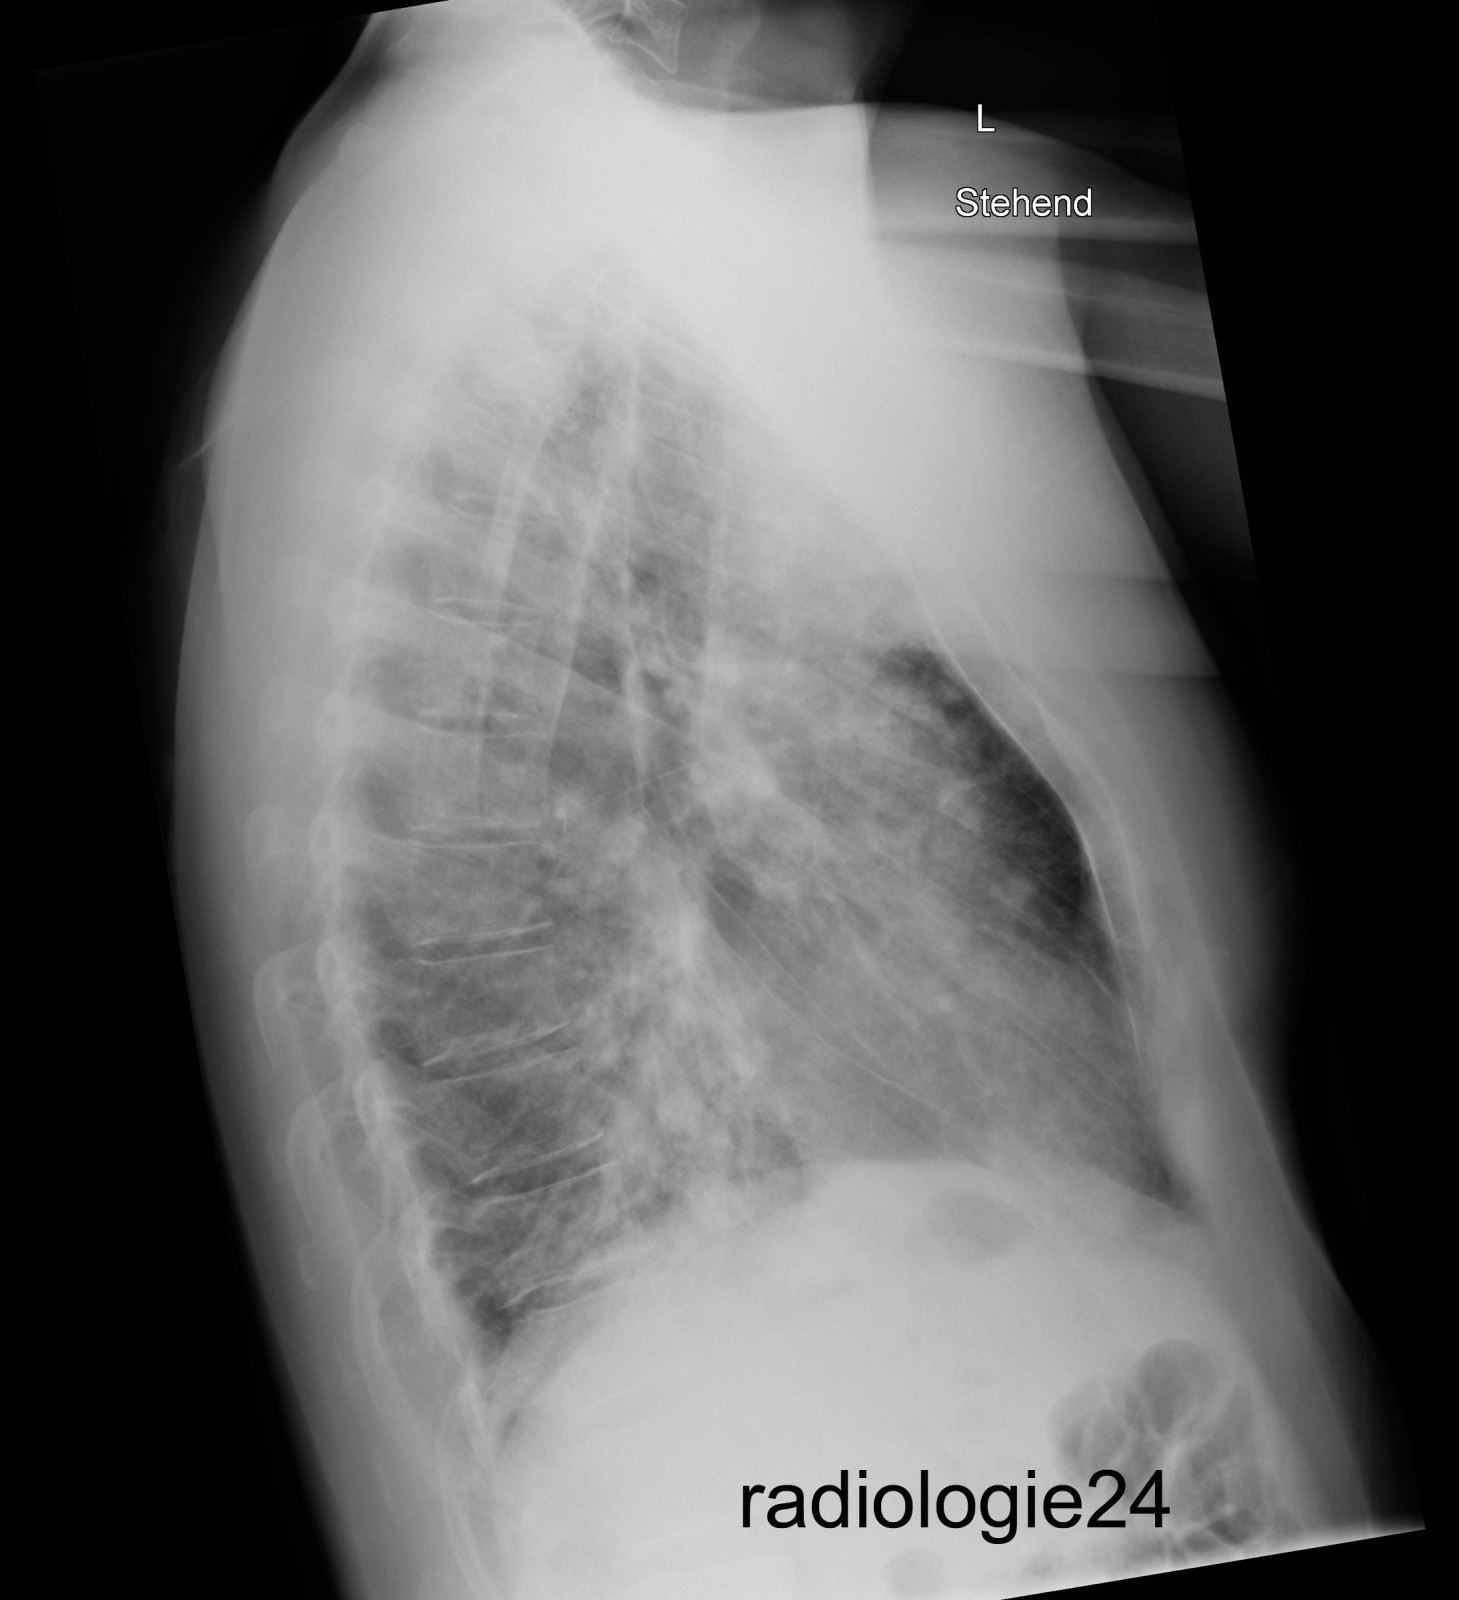

Röntgenfall des Monats August 2018 mit Auflösung

40 jähriger Patient Triathlon Sportler. Bei einem Wettkampf muss der Patient wegen akut auftretender Dyspnoe nach dem Schwimmen, die Disziplin des Fahrradfahrens abbrechen und kann den Triathlon nicht beenden. Einlieferung in die Notaufnahme des nächstliegenden Spital. Ihre Diagnose? Weitere radiologische Diagnostik notwendig?

Bild vergrössern